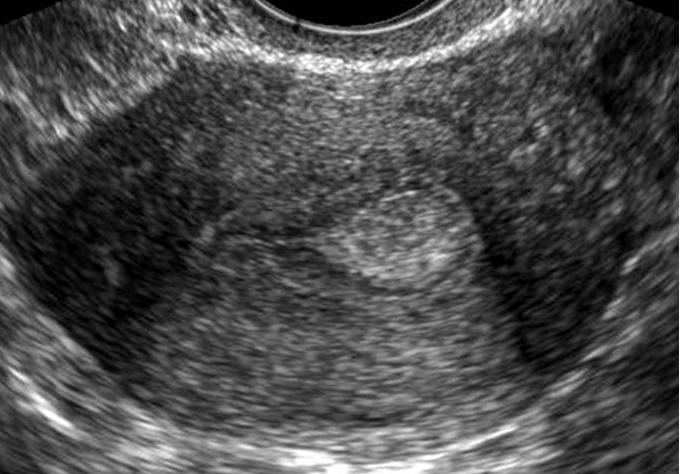

- The best imaging techniques for evaluating the endometrial cavity are hysteroscopy and sonohysterography (SHG) - the latter sometimes called "saline infusion sonography", a contrast ultrasound technique that can also be performed with gel.

Video demonstrating performance of sonohysterography (SHG) and the relationship to an endometrial polyp seen hysteroscopically